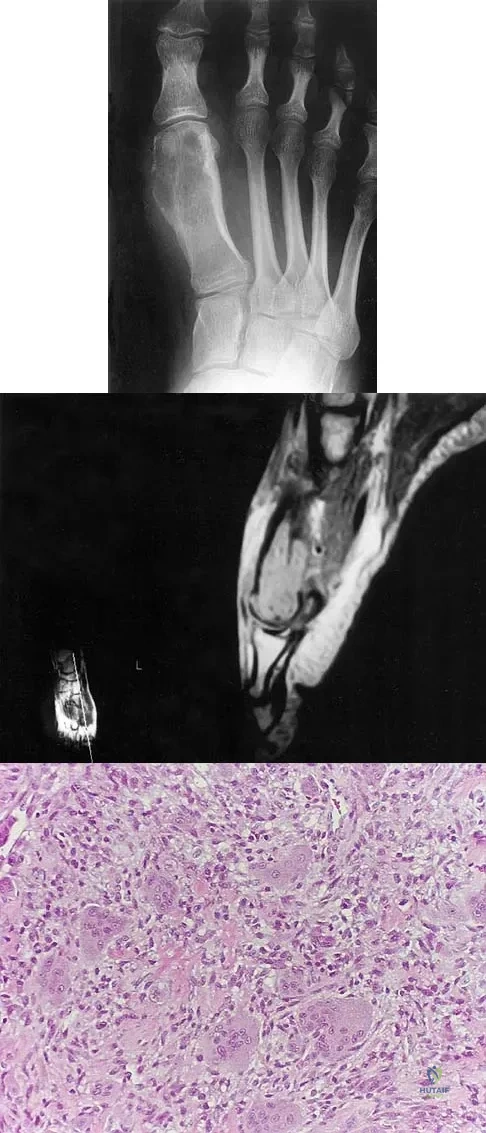

A 20-year-old patient has foot pain. A radiograph and T1-weighted MRI scan are shown in Figures 8a and 8b. A biopsy specimen is shown in Figure 8c. Treatment should consist of